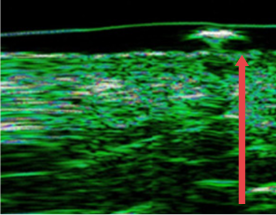

ปรับปรุงชั้นหนังแท้ของผิวหนังที่บางลงเนื่องจากความชรา การทำหัตถการผิวบ่อยๆ และการกระตุ้นจากภายนอก

ก่อนฉีด

หลังฉีด 4 เดือน

(ชั้นหนังแท้หนาขึ้น 12%)

หลังฉีด 7 เดือน

(ชั้นหนังแท้หนาขึ้น 27% )